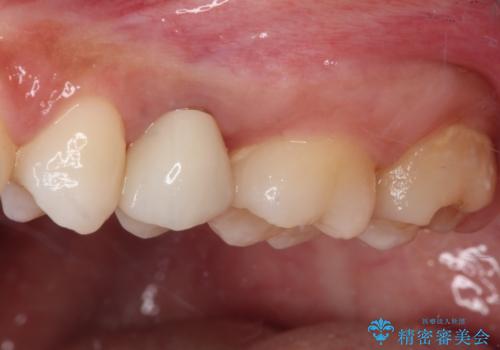

その後骨形成処置を行い、治癒を待って補綴治療を行うこととしました。

かなり深い位置にまで虫歯が及んでいたため、かなりの量を引っ張り出す必要があり、残された歯根は短く小さい状態となりました。

今後も定期的にレントゲンを撮るなど、経過を追っていく必要があります。